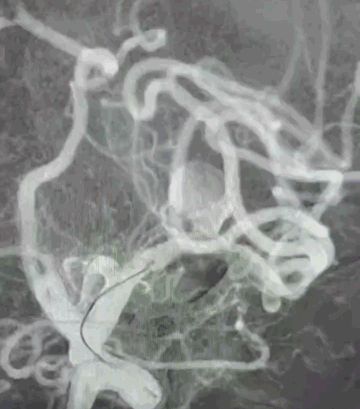

Tubridge Case 2